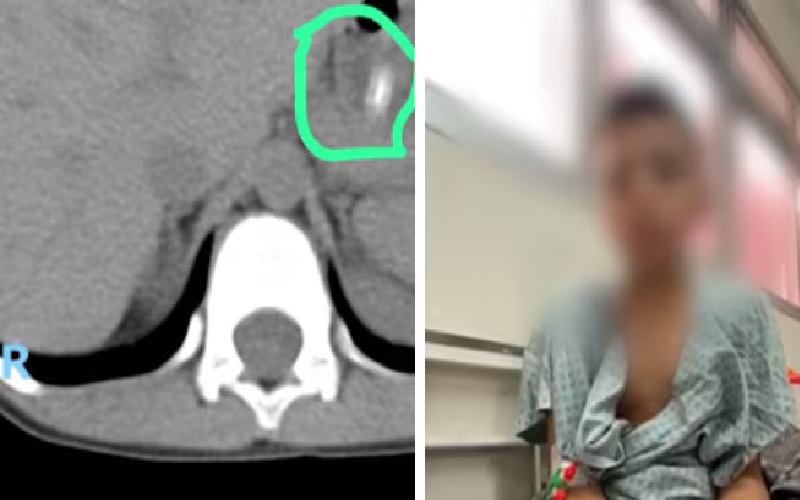

Foto:Reprodução | A criança foi levada ao hospital, onde exames revelaram a presença do lápis no estômago.

A criança foi levada ao hospital, onde exames revelaram a presença do lápis no estômago. Segundo os médicos, o objeto já está percorrendo o intestino, e há preocupação de que possa perfurá-lo. Por conta da idade do menino, a cirurgia só será indicada em último caso. Os profissionais acompanham diariamente o percurso do lápis.